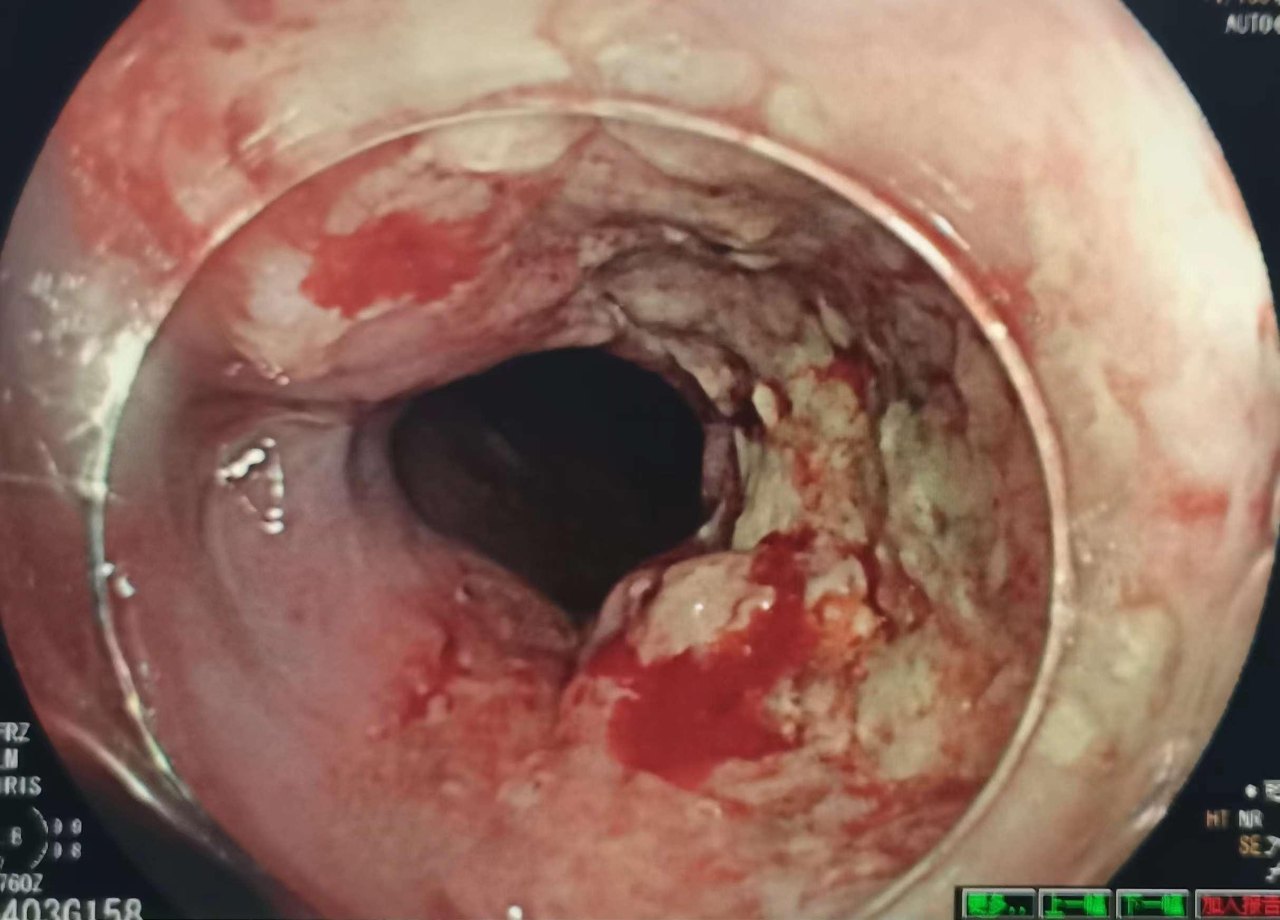

胃癌进展期

食管进展期肿瘤